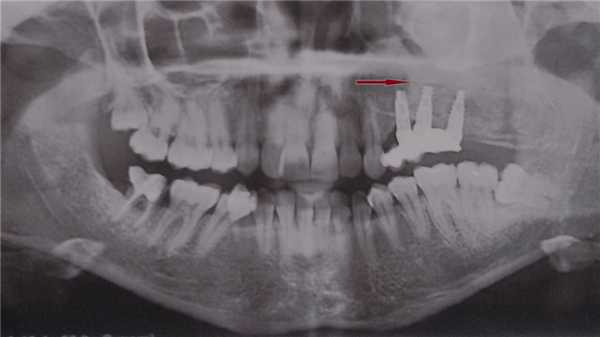

(Слева) На кадрированной панорамной рентгенограмме определяется ФД нижней челюсти справа. Смещение кверху нижнечелюстного канала - патогномоничный признак. Нижний край нижней челюсти вздут, кортикальные пластинки изменены в соответствии с картиной поражения костной ткани. Формирующийся третий моляр смещен кзади.

(Справа) На аксиальной КТ в костном окне определяется картина «матового стекла», характерная для ФД, с вздутием альвеолярного отроака верхней челюсти слева. Щечная и язычная кортикальные пластинки неразличимы. Патологический очаг не пересекает среднюю линию. (Слева) На корональной КЛКТ определяется полиостотическая ФД нижней и верхней челюсти, клиновидной кости, скуловой кости справа. Зернистая картина поражения костной ткани сочетается с «матовым стеклом». Пораженные кости увеличены, но их форма в целом сохранена.

(Справа) На корональной КТ в костном окне определяется ФД, окружающая левую верхнечелюстную пазуху, приводящая к уменьшению ее объема и элевации дна носовой ямки слева. Поражение также распространяется кверху и приводит к смещению кверху дна глазницы. (Слева) На панорамной рентгенограмме определяется ФД в виде «апельсиновой кожуры» между корнями премоляров нижней челюсти слева. Очаг имеет четкие края и смещает корни зубов в стороны.

(Справа) На КЛКТ у этого же пациента определяется истончение и вздутие щечной кортикальной пластинки. Обратите внимание на изменение твердой пластинки и верхней кортикальной пластинки нижнечелюстного канала в соответавии с картиной поражения кости. Канал не смещен и не сдавлен.